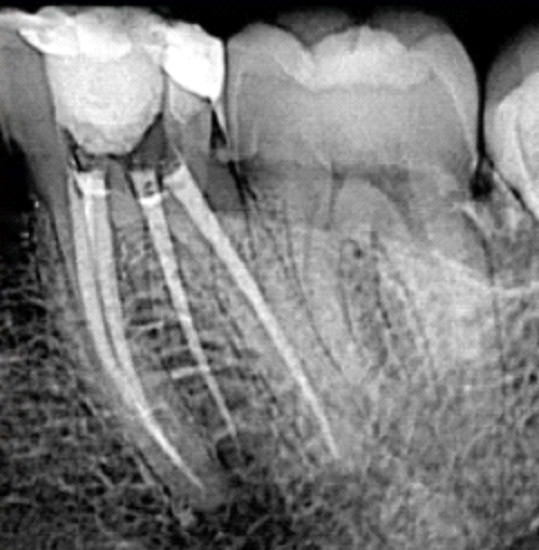

Primeiro, o dente é acessado internamente. Em seguida, todo o tecido inflamado ou necrosado é removido, e os canais são cuidadosamente limpos e modelados. Durante esse processo, utilizam-se soluções antissépticas para eliminar bactérias e resíduos orgânicos (SIQUEIRA; RÔÇAS, 2009).

Após a limpeza, os canais são vedados com um material obturador flexível, geralmente à base de guta-percha, que impede a recontaminação. Por fim, o dente é reconstruído, devolvendo função e estética ao sorriso (TORABINEJAD; WALTON, 2015).

Nem todo canal é igual

Cada tratamento de canal é único. Existem dentes com apenas um canal, enquanto outros — especialmente pré-molares e molares — podem apresentar dois, três, quatro ou até mais canais, o que aumenta a complexidade do procedimento (VERTUCCI, 2005).